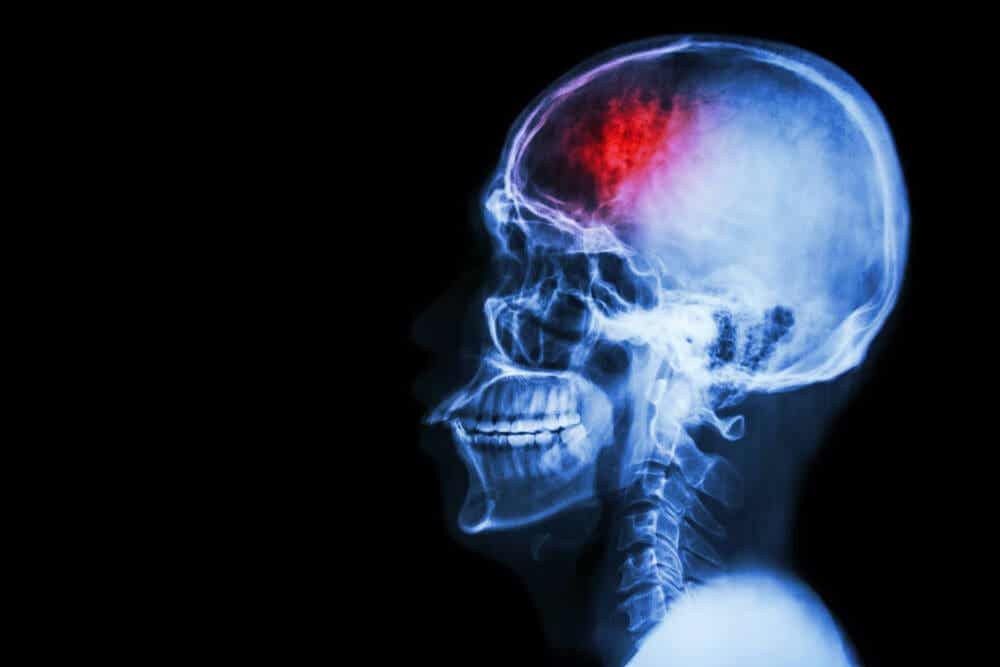

Intracranial Hematoma: What Is It and How Is It Treated?

This problem develops when blood accumulates inside the skull bones. The locations of this blood collection are varied, and the clinical picture will change according to those positions.

One of the problems of these hematomas is the pressure they generate on a sensitive organ such as the brain. This increased tension hurts the neurons and complicates their functioning.

Also known as intraparenchymal hematoma. It’s located within the brain tissue, in the middle of the neurons, hence its name. It can originate in trauma, but also when strokes happen due to arterial ruptures or the presence of a congenital malformation.

When doctors detect an intracranial hematoma, they establish its size and position. This is accomplished by imaging techniques such as CT or MRI.